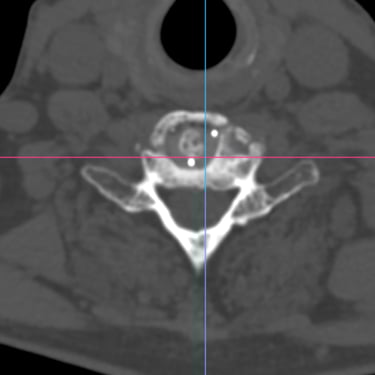

🧠 Discopatía y Estenosis Cervical | Cirugía de Discectomía Cervical Anterior y Fusión (ACDF).

La discopatía y estenosis cervical generan dolor, hormigueo y debilidad por compresión nerviosa. La cirugía ACDF (Discectomía Cervical Anterior y Fusión) retira el disco dañado, descomprime médula y raíces, y estabiliza con injerto y placa. Este procedimiento alivia síntomas, restaura función y mejora la calidad de vida.